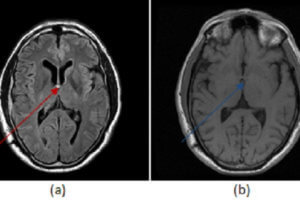

Obstructive Hydrocephalus – Colloid Cyst

Hydrocephalus refers to enlargement of the ventricular system and two broad categories are recognized – communicating and noncommunicating. Read more »